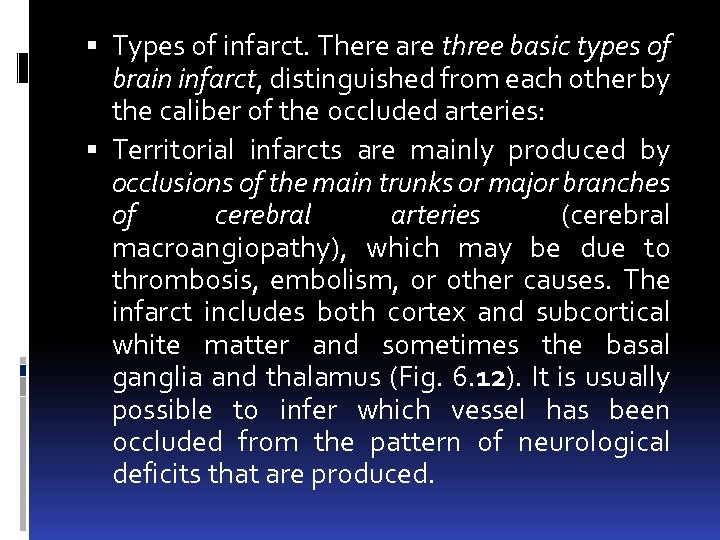

Types of infarct. There are three basic types of brain infarct, distinguished from each other by the caliber of the occluded arteries: Territorial infarcts are mainly produced by occlusions of the main trunks or major branches of cerebral arteries (cerebral macroangiopathy), which may be due to thrombosis, embolism, or other causes. The infarct includes both cortex and subcortical white matter and sometimes the basal ganglia and thalamus (Fig. 6. 12). It is usually possible to infer which vessel has been occluded from the pattern of neurological deficits that are produced.

Types of infarct. There are three basic types of brain infarct, distinguished from each other by the caliber of the occluded arteries: Territorial infarcts are mainly produced by occlusions of the main trunks or major branches of cerebral arteries (cerebral macroangiopathy), which may be due to thrombosis, embolism, or other causes. The infarct includes both cortex and subcortical white matter and sometimes the basal ganglia and thalamus (Fig. 6. 12). It is usually possible to infer which vessel has been occluded from the pattern of neurological deficits that are produced.